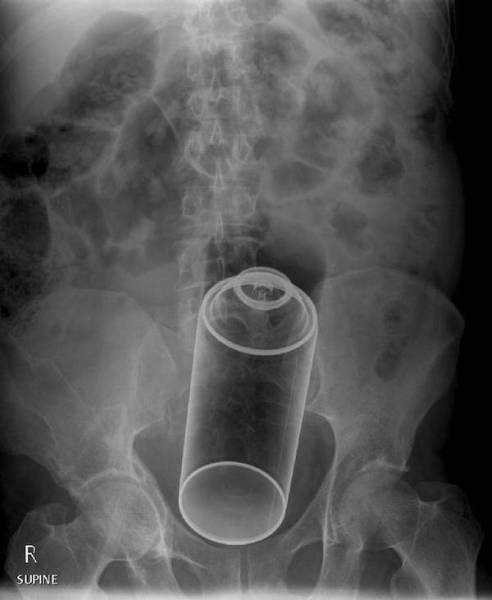

#19 Vibraattori